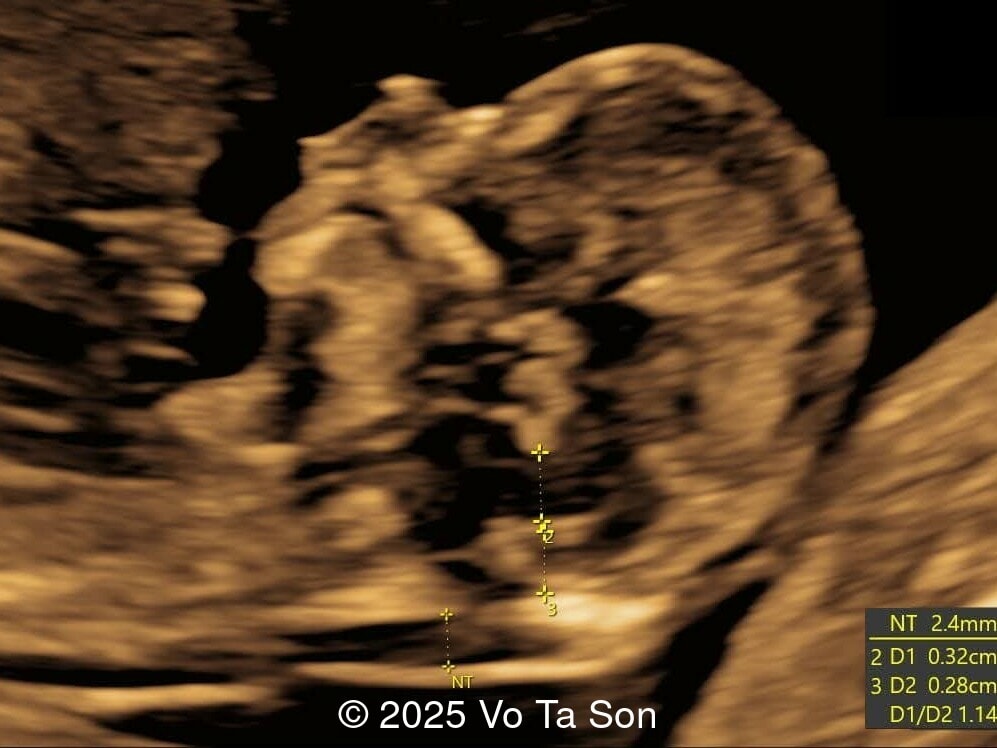

• Thin nasal bone

• Open spina bifida in the sacral region with dry brain sign, crash sign, BS/BSOB >1, and a lesion at the sacral coccygeal spine. The spinal lesion observed in the sacral region is characterized by a posterior vertebral arch defect and a protruding meningeal sac.